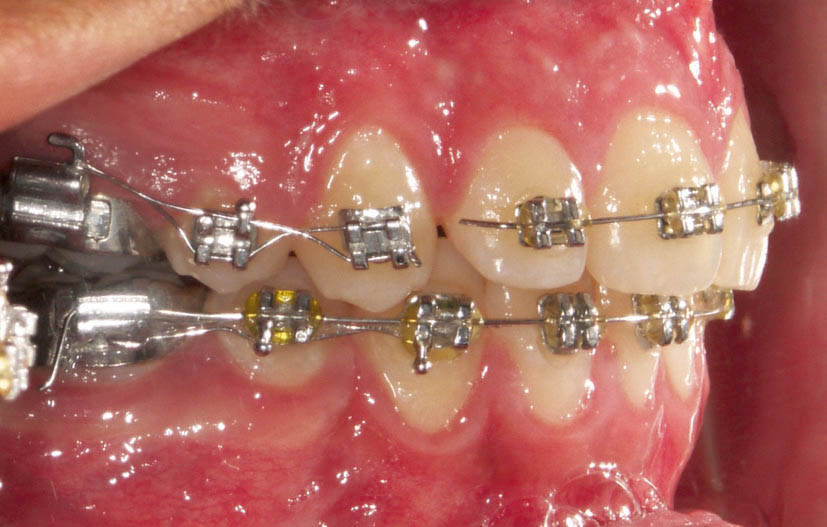

در یک اکلوژن 5mm کلاسII (شکل 126-2 و 127-2) وقتی پرمولر پایین کشیده شود خلفیهای پایین حدود نیم کاسپ (3.5mm) جلو میآیند (شکل 128-2). اگر خلفیهای بالا اصلاً جلو نیایند باز به رابطه کلاسI نمیرسید (شکل 129-2 و 130-2).

شکل 126-2: اکلوژن 5mm کلاسII

شکل 127-2: اکلوژن 5mm کلاسII